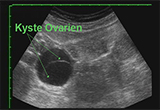

Le kyste ovarien : les symptômes liés et les traitements pour s'en débarrasser

Le plus souvent bénin, le kyste ovarien peut être parfois la cause d'une tumeur maligne. Découvrez dans la suite ses symptômes, les techniques de diagnostique ainsi que les traitements envisageables pour lutter contre.